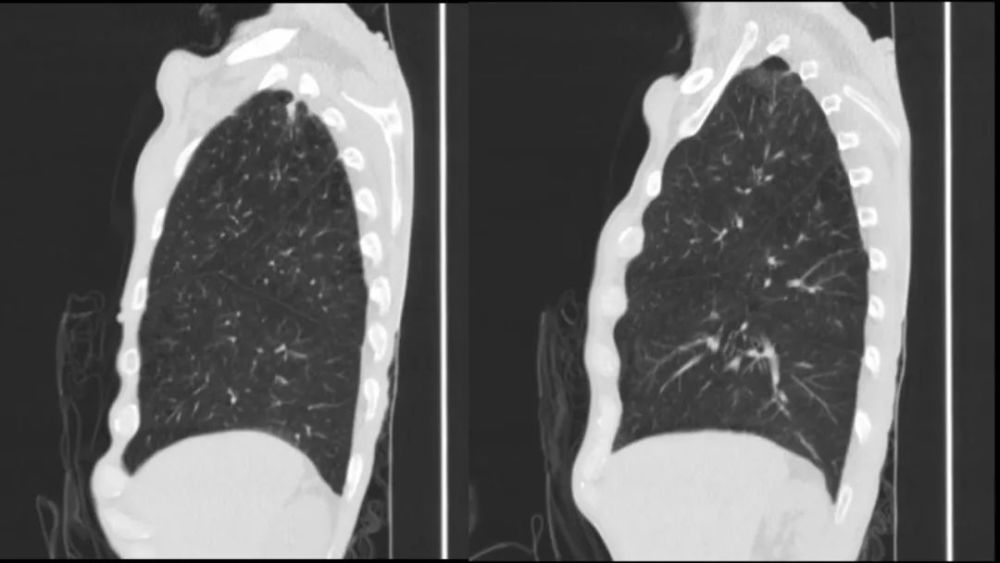

垂直裂

Vertical fissure line in the lung

很少>1mm ,

起于肋膈?或其附近区域 , 向上略向肺?偏向走形 在水平裂前或至于水平裂上

绝大部分在右肺 , 左肺偶?